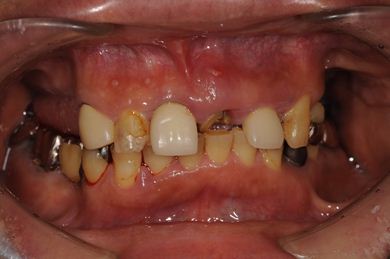

| 性別/年齢 | 男性 / 58歳 | ||||||||||||||||||||||||||||||||

| 主訴 | 上前歯欠損部のインプラント治療を希望。 | ||||||||||||||||||||||||||||||||

| 治療方針 | 右上奥はソケットリフトにて上顎洞拳上してインプラント埋入を可能にし、上顎前歯部は骨再生法によりインプラント治療を行う。その他、補綴により口腔内全体の機能的審美的回復を行う。 | ||||||||||||||||||||||||||||||||

| 治療内容 | インプラント8本(GBR、ソケットリフト)、ハイブリッドセラミッククラウン17本(セラミック用土台5本) | ||||||||||||||||||||||||||||||||